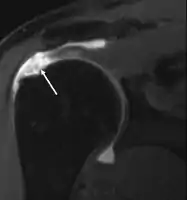

MRI

Magnetic resonance imaging (MRI) and ultrasound[47] are comparable in efficacy and helpful in diagnosis, although both have a false positive rate of 15–20%.[48] MRI can reliably detect most full-thickness tears, although very small pinpoint tears may be missed. In such situations, an MRI combined with an injection of contrast material, an MR-arthrogram, may help to confirm the diagnosis. It should be realized that a normal MRI cannot fully rule out a small tear (a false negative) while partial-thickness tears are not as reliably detected.[49] While MRI is sensitive in identifying tendon degeneration (tendinopathy), it may not reliably distinguish between a degenerative tendon and a partially torn tendon. Again, magnetic resonance arthrography can improve the differentiation.[49] An overall sensitivity of 91% (9% false negative rate) has been reported, indicating that magnetic resonance arthrography is reliable in the detection of partial-thickness rotator cuff tears.[49] However, its routine use is not advised, since it involves entering the joint with a needle, with the potential risk of infection. Consequently, the test is reserved for cases in which the diagnosis remains unclear.